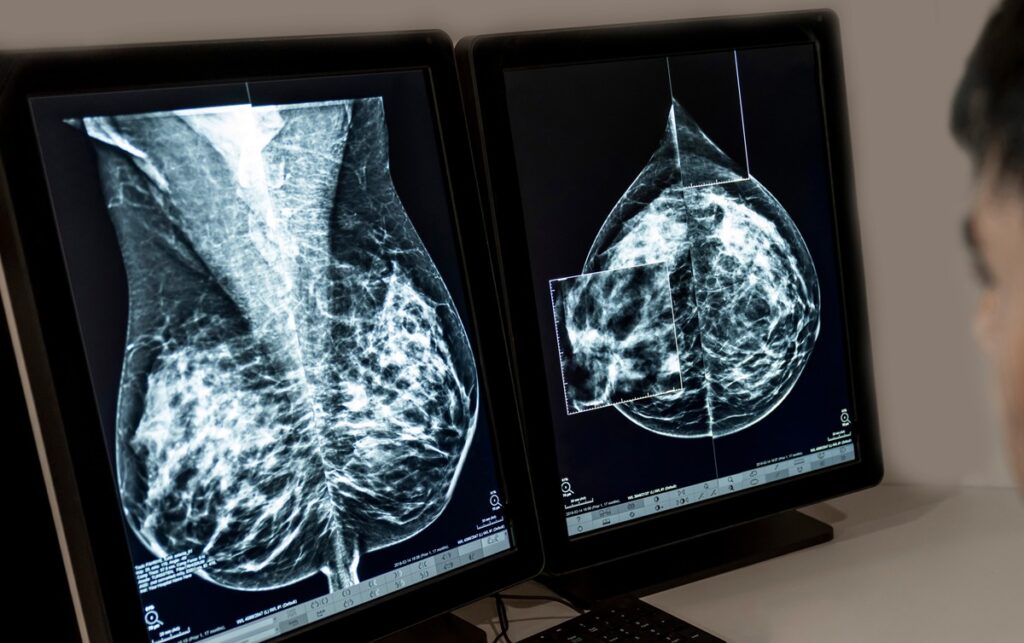

Qual Exame Detecta Mais Câncer de Mama?

Você já se perguntou qual exame é mais eficaz para detectar o câncer de mama? Essa é uma das dúvidas mais comuns que recebo no consultório e nas redes sociais: “Doutora, qual exame é melhor para mim, a mamografia, o ultrassom ou a ressonância magnética?”. Muitas mulheres chegam com a ideia de que um exame […]

Mamografia: Quando Fazer e Por Que é Essencial

A mamografia é um exame que gera muitas dúvidas e, para algumas mulheres, até um certo receio. No meu consultório, percebo que a falta de informação clara pode transformar um ato de cuidado em uma fonte de ansiedade. Vejo diariamente o impacto positivo deste exame na vida das mulheres – desde a tranquilidade de um […]